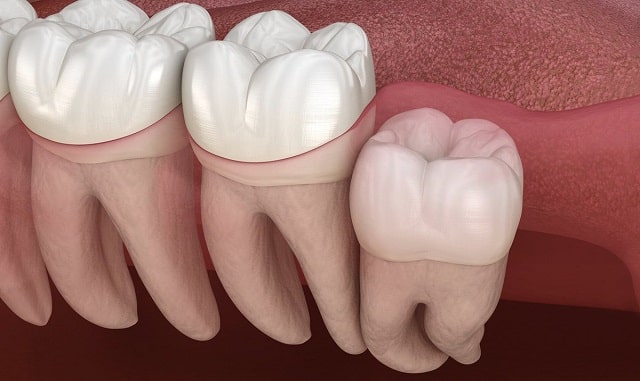

Ретенция бывает:

- Полная — зуб полностью скрыт под десной и костной тканью.

- Частичная — зуб частично прорезался, но не до конца.

Чаще всего ретинированы именно третьи моляры (зубы мудрости), поскольку для них может просто не хватить места в челюсти. На втором месте — клыки, особенно верхние, которые играют важную роль в формировании прикуса.